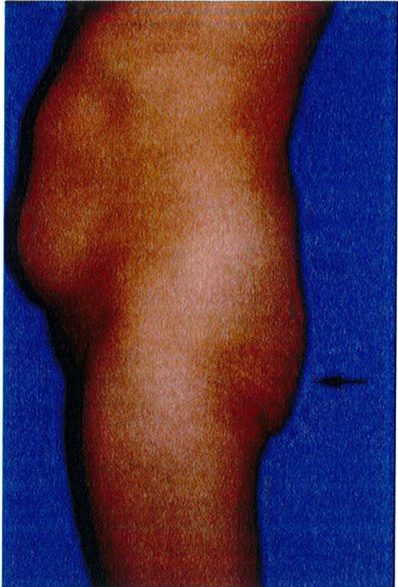

Bước cuối cùng khi đánh giá vùng mông là đánh giá tình trạng sa mông. Đế đánh giá, nên đứng ỏ phía bên để nhìn và phân loại sa mông (từ không sa đến có sa), cả 2 loại này đều được phân loại thành 3 phân lớp phía dưới chúng. Việc phân loại này quyết định xem nên thực hiện quy trình nào cho bệnh nhân.

Ở những bệnh nhân không có sa mông, toàn bộ vùng mông nằm trên nếp lắn mông và không có phần da thừa nằm dưới nếp lằn.

Phân loại sa mông

Phân loại này được áp dụng khi có vùng da sa xuống dưới nếp lắn mông và chúng được chia thành 3 giai đoạn I, II, III (Hình 28).

Ptosis Grade I 0°-10°: Sa mông GĐ 1 0°-10° Ptosis Grade II 10º-30º Ptosis Grade III 30° or greater: Sa mông GĐ III 30° hoặc hơn

Ptosis Grade II 10°- 30°

Hình. 28. Giai đoạn I, II, III của bệnh nhân có tình trạng sa mông. Ở giai đoạn I, góc tạo bởi nếp da nhỏ hơn 10 độ. Ở giai đoạn II, focs này rơi vào khoảng từ 10- 30 độ. Còn ở giai đoan III, góc tao bởi nếp da lớn hơn 30 đô.